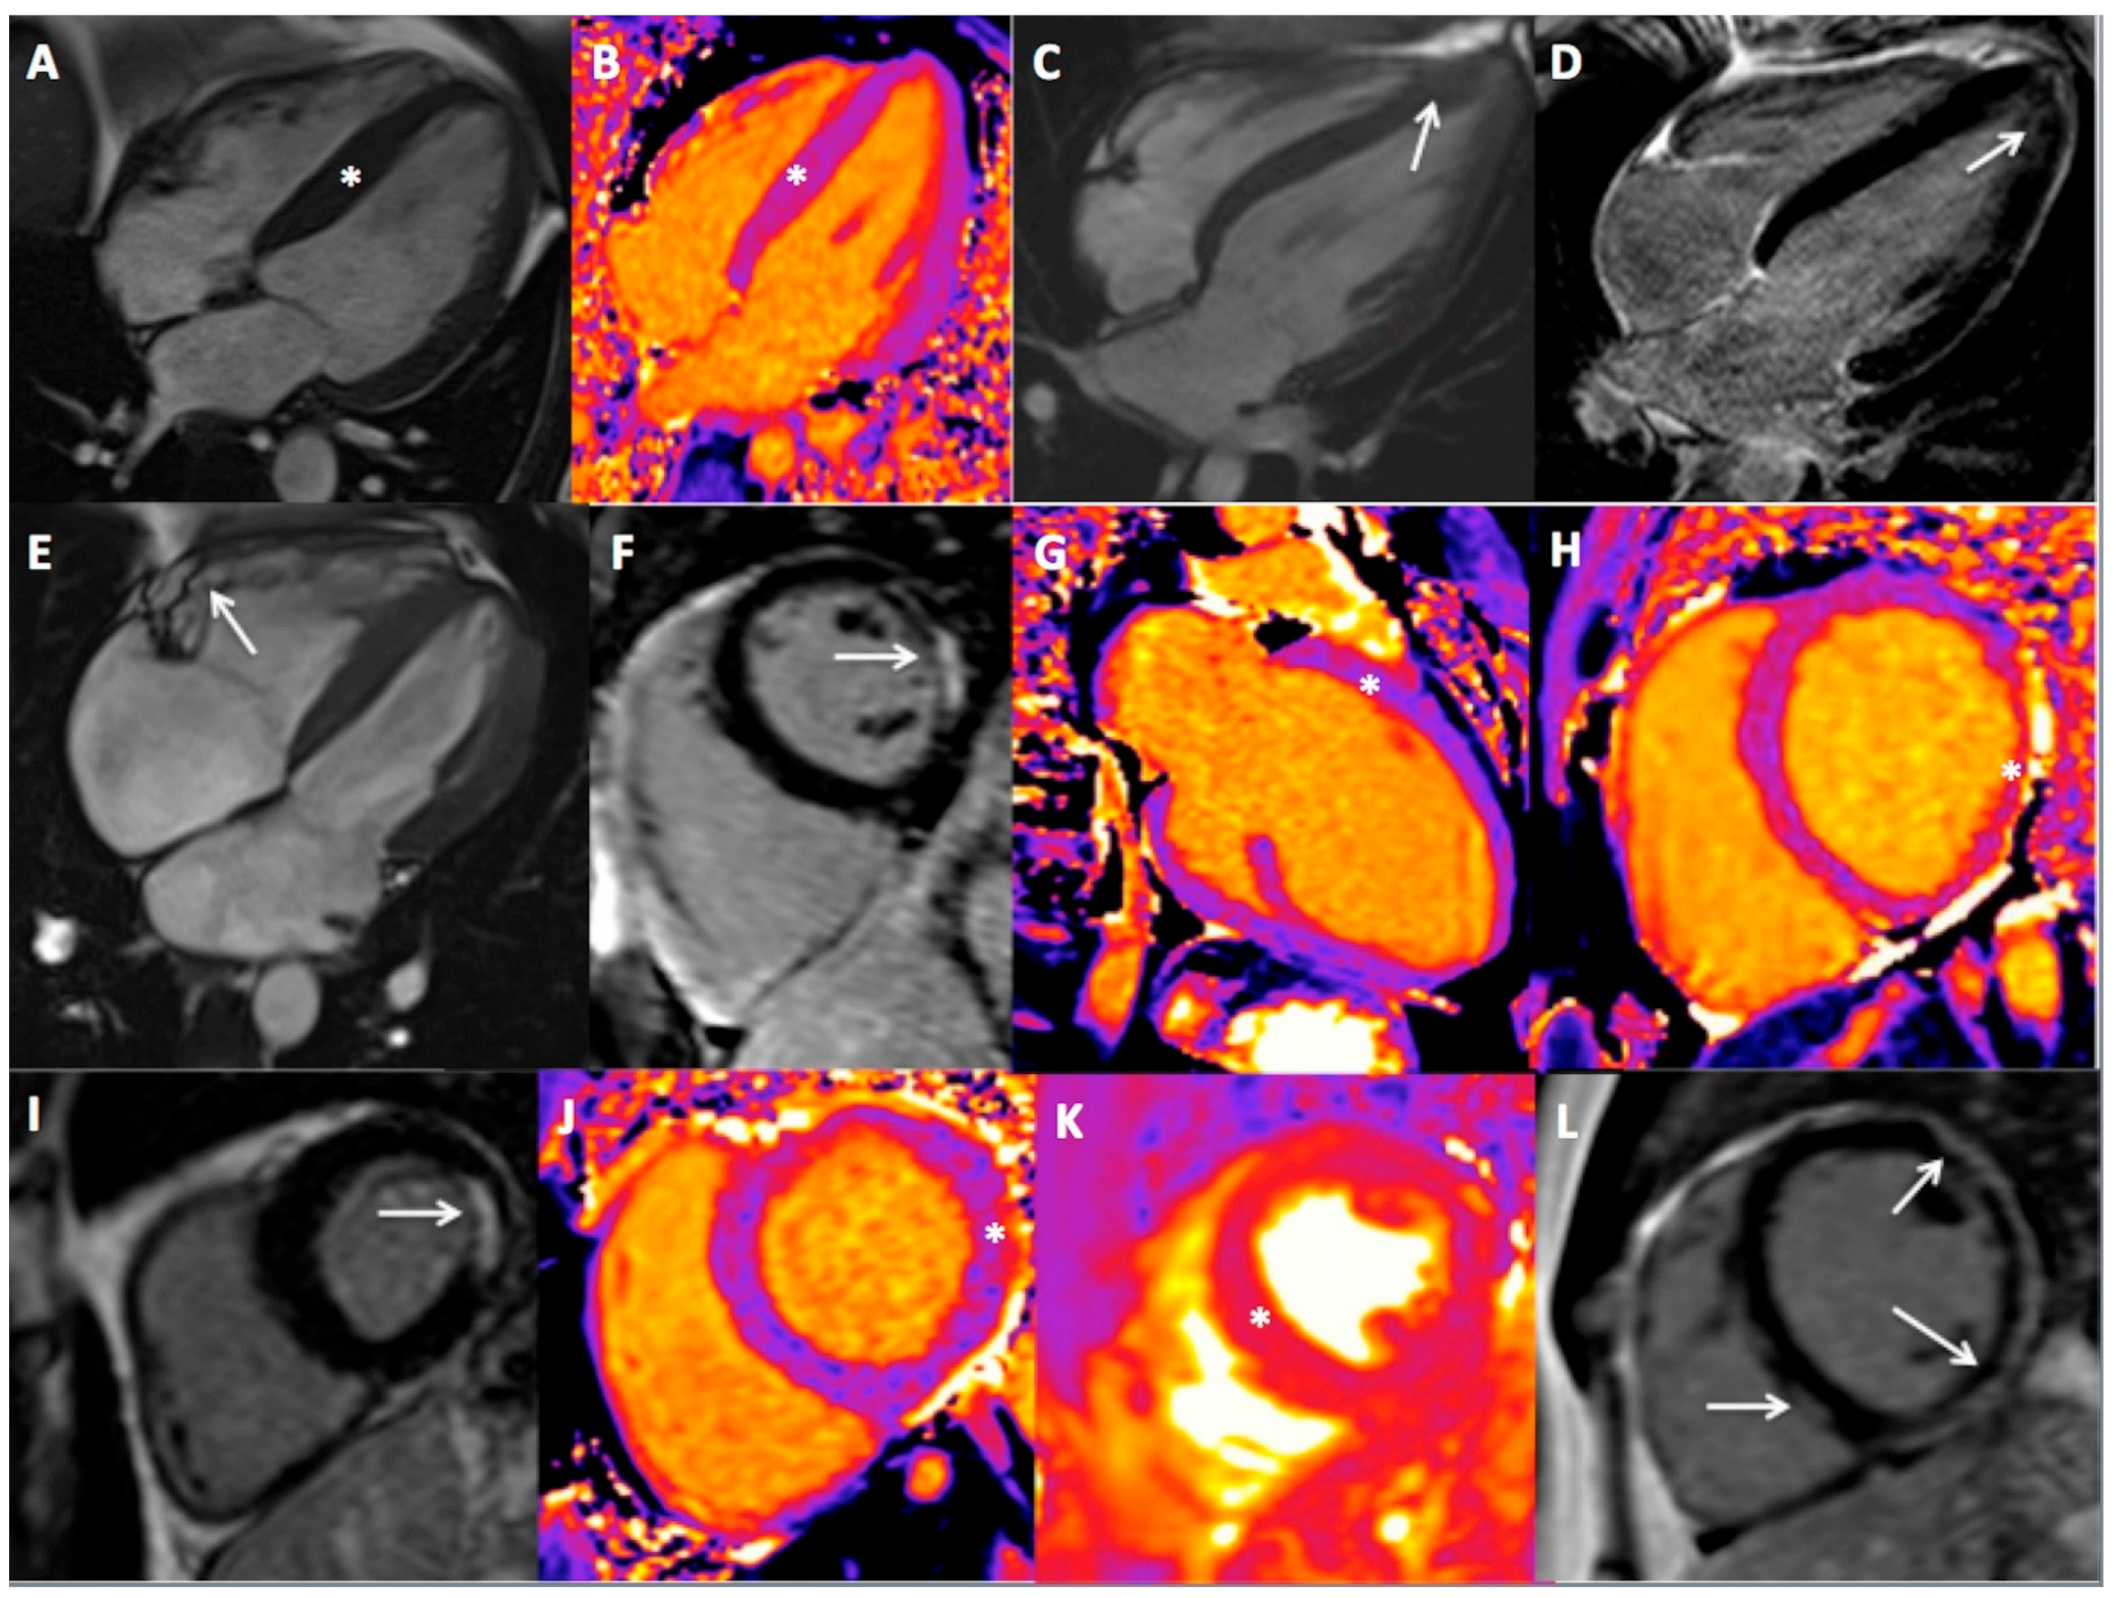

3.2. CMR Findings

3.3. Athlete’s Heart and CMR Result

| CMR result | |||

| Disease (n,%) | 19 (32) | 47 (49) | 0.05 |

| Type of disease (n, %) | |||

| HCM | 1 (2) | 10 (11) | 0.05 |

| HCM apical | 2 (3) | 4 (4) | 1.00 |

| All HCM | 3 (5) | 14 (15) | 0.22 |

| DCM | 3 (5) | 3 (3) | 0.68 |

| AC | 1 (2) | 3 (3) | 1.00 |

| LVNC | 0 (0) | 0 (0) | - |

| All cardiomyopathy | 7 (12) | 20 (21) | 0.21 |

| Prior MI | 0 (0) | 6 (6) | 0.08 |

| Acute/prior myocarditis | 7 (12) | 14 (14) | 0.79 |

| Other findings * | 5 (8) | 7 (7) | 0.95 |